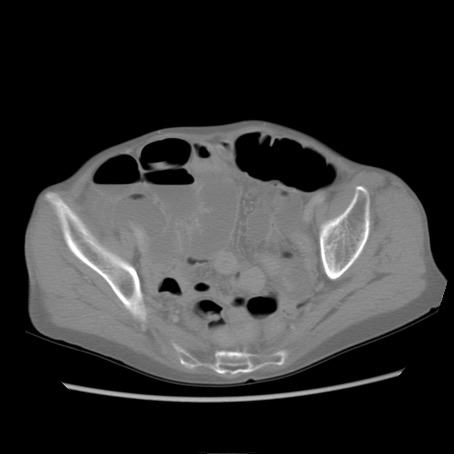

症例25(横断像)

症例

【症例】80歳代女性

【主訴】胸のつかえ感

【現病歴】約9時間前に食後から胸のつかえた感じあり、嘔吐あり、来院。

【既往歴】胃癌(全摘)、胆摘、虫垂炎

【身体所見】心窩部に圧痛あり、反跳痛なし。

【データ】WBC 5700、CRP 0.05